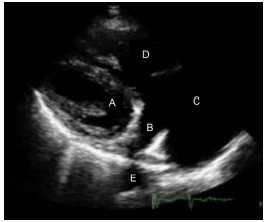

Analise a figura a seguir.

Os pontos A, B, C, D e E, correspondem, respectivamente, à(ao)